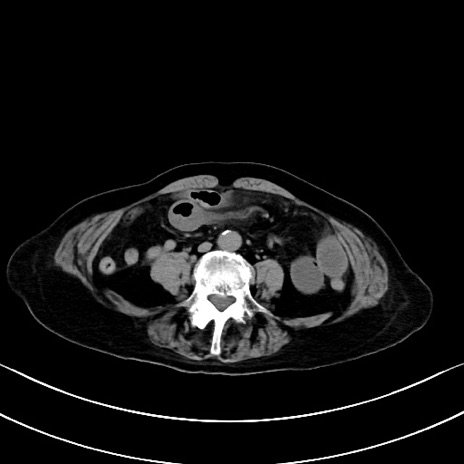

症例40(横断像)他院1日前

横断像